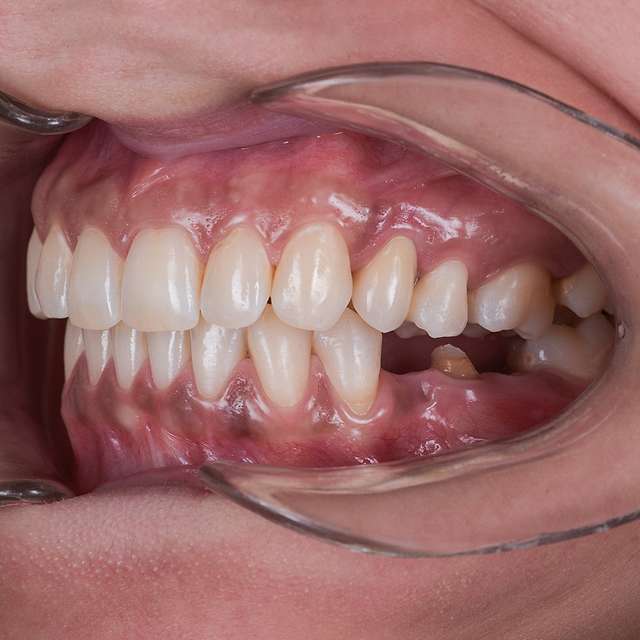

Ghidurile chirurgicale sunt utilizate pentru o siguranta si o precizie sporita in cazurile complexe care necesita tratamentul cu implanturi dentare. Ghidurile sunt printate 3D, conform planificarii digitale a chirurgiei, folosind un software specializat si radiografia 3D a pacientului. (computerul tomograf)

Pentru un rezultat estetic ideal, design-ul final trebuie sa fie intotdeauna referinta pentru chirurgie. Design-ul si computerul tomograf al pacientului sunt compilate pentru a primi pozitia ideala a implanturilor dentare

Chirurgia ghidata este sigura si precisa. Ghidul chirurgical este recomandat in cazurile cu un nivel ridicat de dificultate, sau in cazurile complexe, pentru a minimiza riscurile si complicatiile.

Cand procedura insertiei implanturilor dentare se realizeaza cu ajutorul chirurgiei ghidate, chirurgia in sine este mai simpla, iar trauma este mai redusa, in special asupra tesuturilor moi. Astfel, obtinem o vindecare mai rapida, si un comfort sporit post operator.